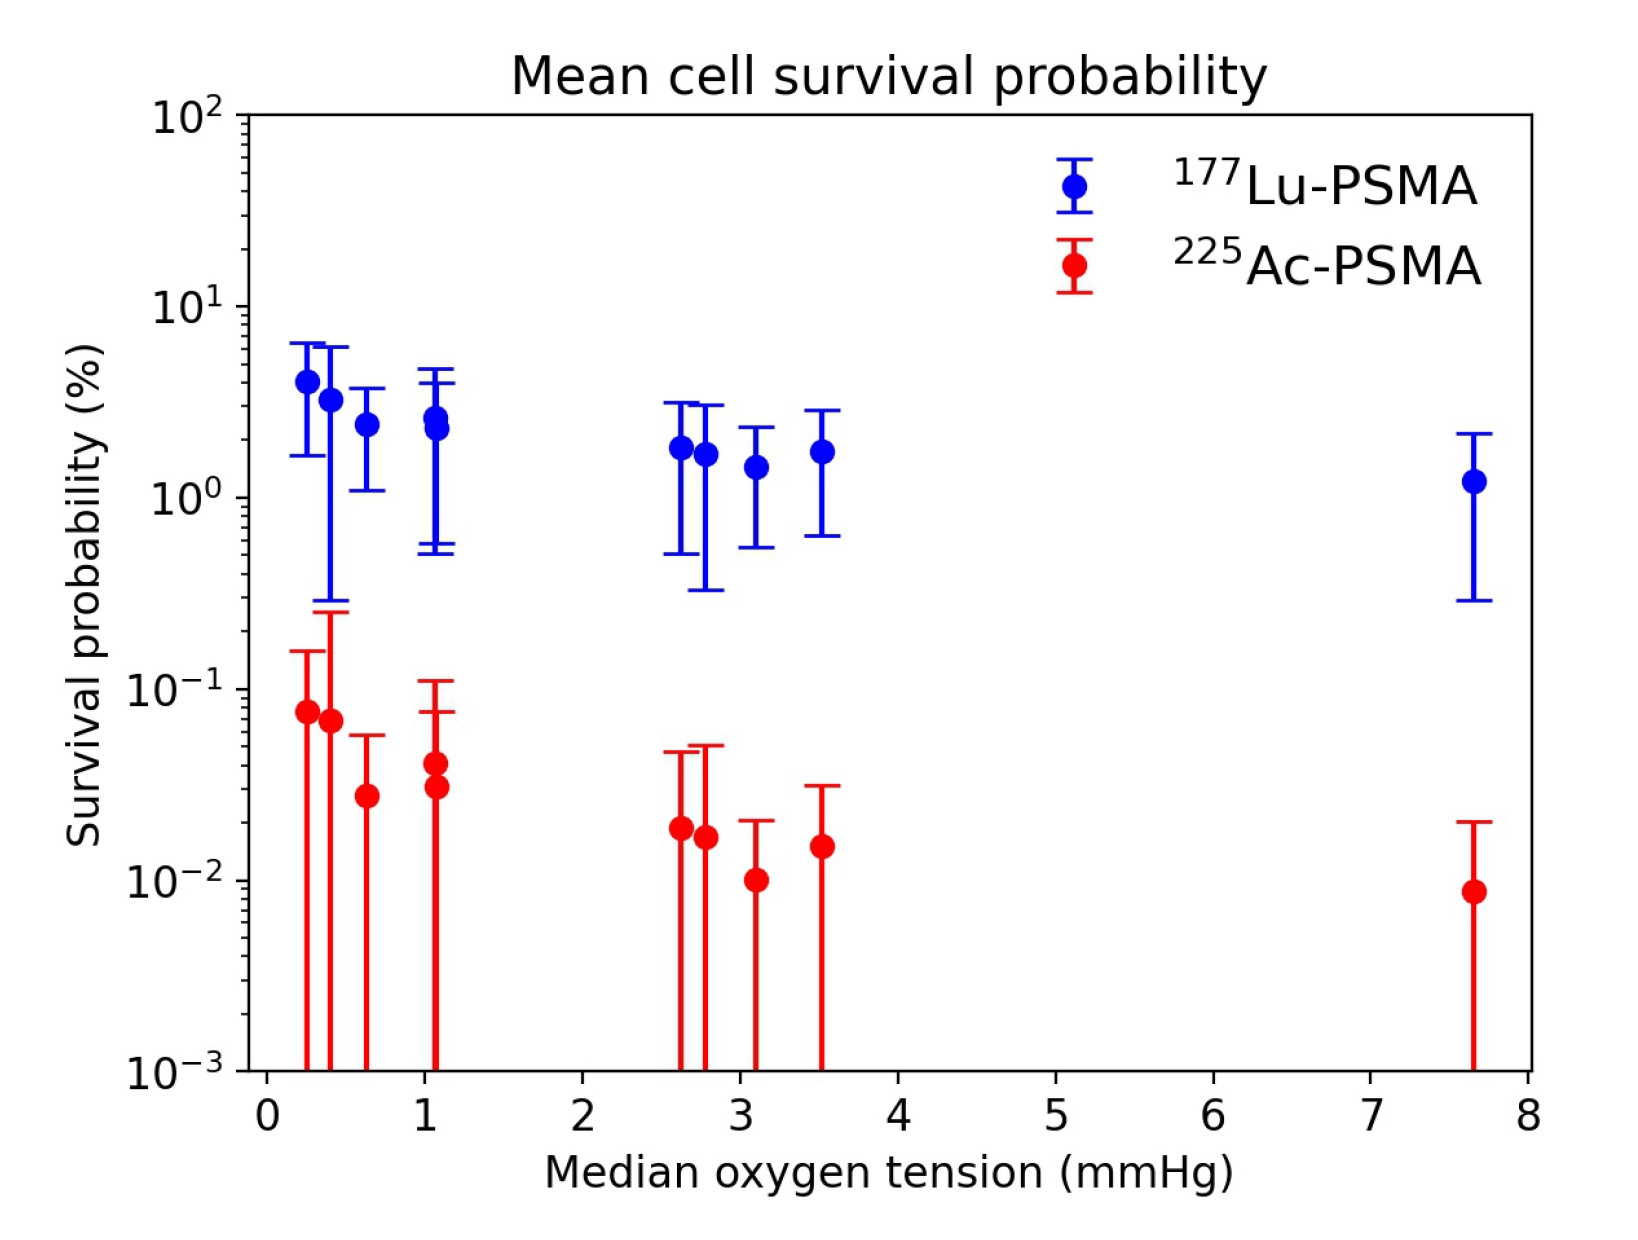

3.3. Radiobiological Efficacy Analysis